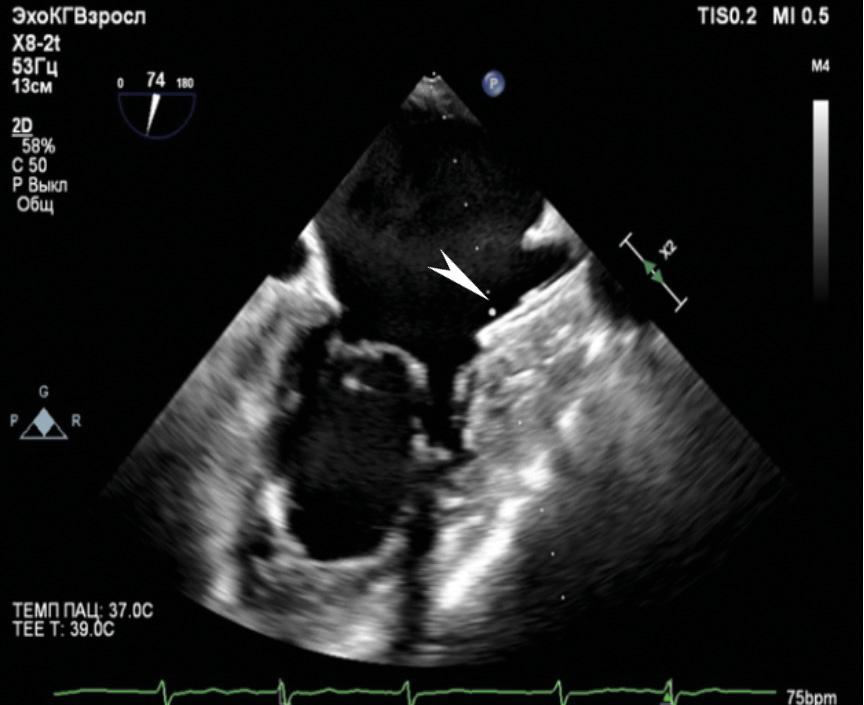

По результатам ЧП ЭхоКГ после вмешательства: в проекции МК визуализируется 1 клипса, митральная регургитация до 1-й степени (площадь струи регургитации 4,5 см2), величина коаптации менее 3 мм. Площадь отверстия МК – 4,7 см2. Кольцо МК = 3,45/3,8 см. Средний диастолический градиент на МК – 2,1 мм рт. ст. Место имплантации клипсы без особенностей. Количество струй регургитации – 1, тип регургитации – эксцентрический, распространяющийся вдоль межпредсердной перегородки. В просвете УЛП визуализируется плотно фиксированный окклюдер. Периферического кровотока по краям окклюдера не выявлено. В месте пункции межпредсердной перегородки визуализируется лево-правый сброс до 3 мм. Данные ЧП ЭхоКГ после вмешательства приведены на рис. 3–5.

Рис. 3. В ушке левого предсердия визуализируется гиперэхогенная структура – окклюдер (указано стрелкой)